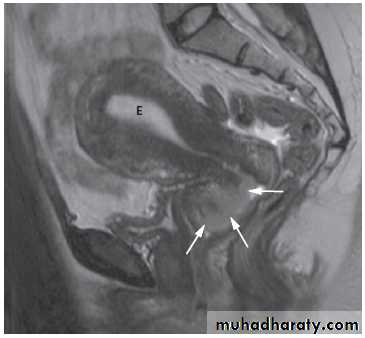

Magnetic resonance imaging is useful to determine the extent of carcinoma of the cervix preoperatively, because the extent (or tumour stage) determines whether the patient is managed with surgery or with chemoradiotherapy.

The observations to be made are whether the tumour is confined to the cervix .

It extends into the parametrium, lymph nodes, rectum, bladder or pelvic side walls .